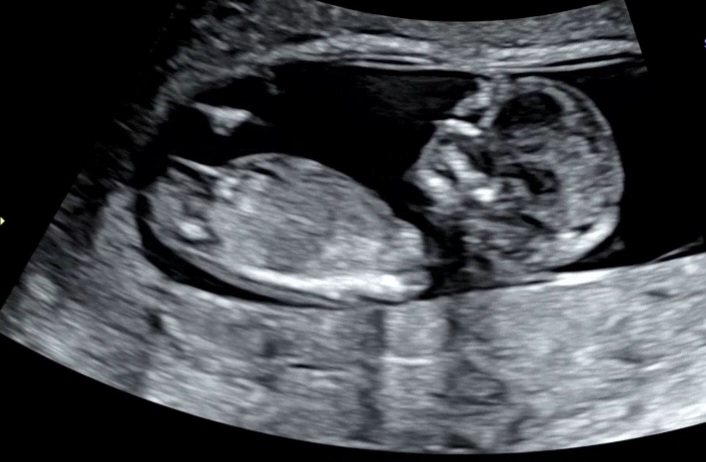

12주차 성별이궁금해요~~ 각도법 보실수있는 분들 계시나요?

각도법을 아무리 공부해도 잘모르겠어요 ㅠㅠ 고수님들 도와주세요~~~

저 사진만 보면 딸이네욤

이렇게만보면 딸같긴한데 정확하려면 16주20주는 되야하니 성별키트 베이킹소다법 요런거 재미로 해보세요~